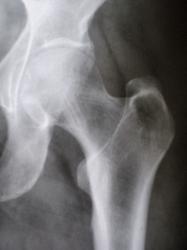

Иллюстрация 2, 3. Медиальнее шейки и проксимального мета-диафиза бедренной кости, на фоне мягких тканей определяются тени двух венозных сосудов, с выраженным отложением солей извести в их стенках.

данное наблюдение не совсем корректное. Обезыствления вен более похоже на ненаучную фантастику. Ход и локализация обезыствленных сосудов соответствуют проекции общей бедренной артерии и ее бифуркации на поверхностную и глубокую артерии(в 90% случаев она расположена ниже головки бедреннной кости. Для наглядности привожу несколько примеров.